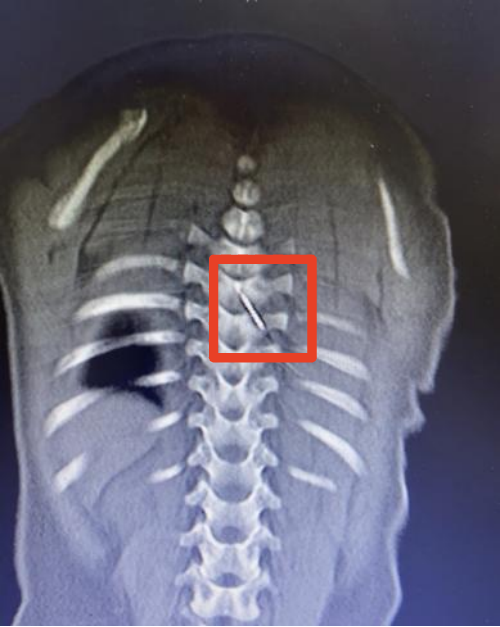

12月5日深夜,一名仅9个月大的男婴琪琪(化名)被紧急送往国家儿童区域医疗中心、安徽省儿童医院救治。原来,一根长约3厘米的缝衣针裹在被子里,竟在孩子睡觉时悄悄“钻”进了他的后背,并随着身体移动不断深入,最终扎入了琪琪的脊柱内,紧贴脊髓的危险区域。

凌晨2点,手术室亮起了无影灯。儿童骨科、麻醉与围术期医学科、儿童重症医学科、影像科多学科专家组成的抢救团队严阵以待。通过三维CT影像,医生们精确还原了针的走行路径和周围解剖结构。当手术刀切开琪琪背部皮肤时,所有人都屏住了呼吸。在高倍显微镜下,在幼儿细小的脊柱解剖结构间小心分离,避开重要血管与神经,最终于脊髓腔外侧安全区域,精准、完整地取出缝衣针。